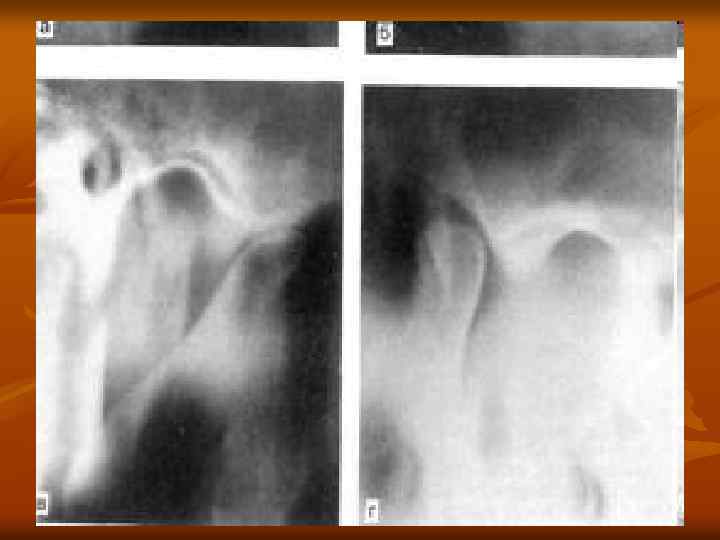

Рентгеновские снимки анкилоза суставов: Как это выглядит